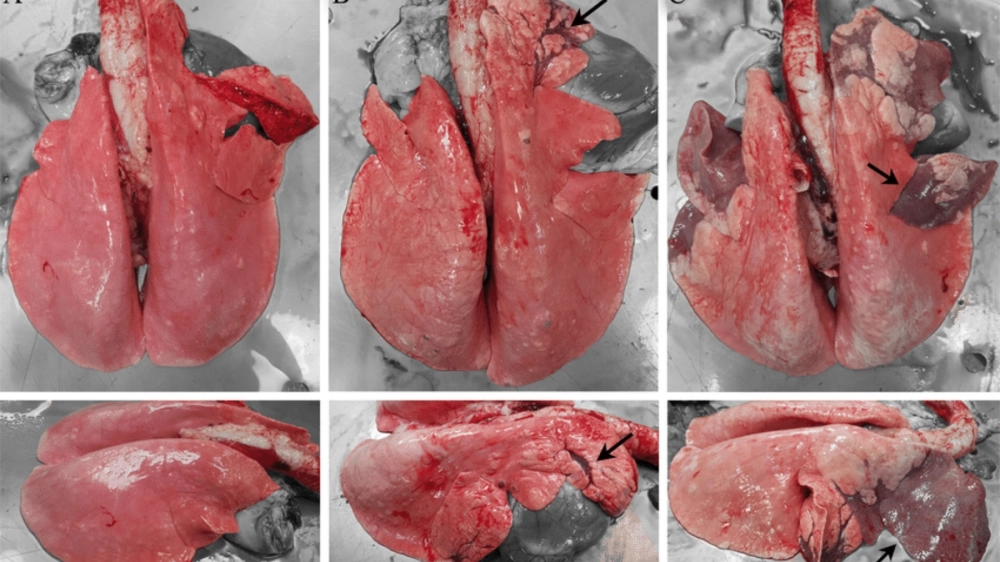

Tổng hợp các hình ảnh về bệnh viêm phổi trực quan nhất

Hình ảnh tổn thương thùy phổi khi chụp X-quang phổi